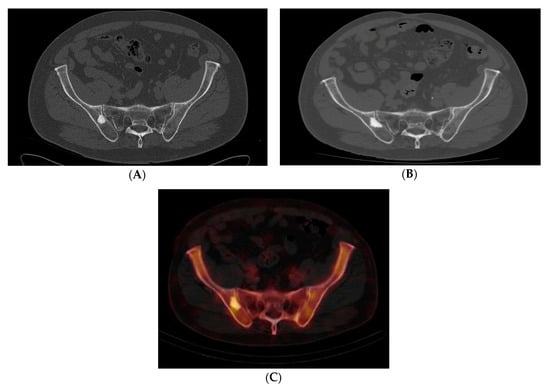

Figure 2. (AC) Case 3. Pelvic axial CT shows an enlarged lesion 10 years after original discovery, which also demonstrated mild radiotracer uptake. (A) Initial pelvic axial CT shows an 18 mm sclerotic lesion in the right ilium near the SI joint. (B) Repeat pelvic CT 10 years later shows enlargement of the lesion to 27 mm. (C) Axial SPECT-CT Tc-99m bone scan demonstrated mildly increased radiotracer in the right iliac bone correlating with the region of the patient’s enlarging bone lesion. Although low-grade central osteosarcoma or osteoblastoma could not be ruled out, we believed atypical BI was the most likely diagnosis. The patient opted for observation rather than bone biopsy. There has been no routine follow up visits over the last 10 months.